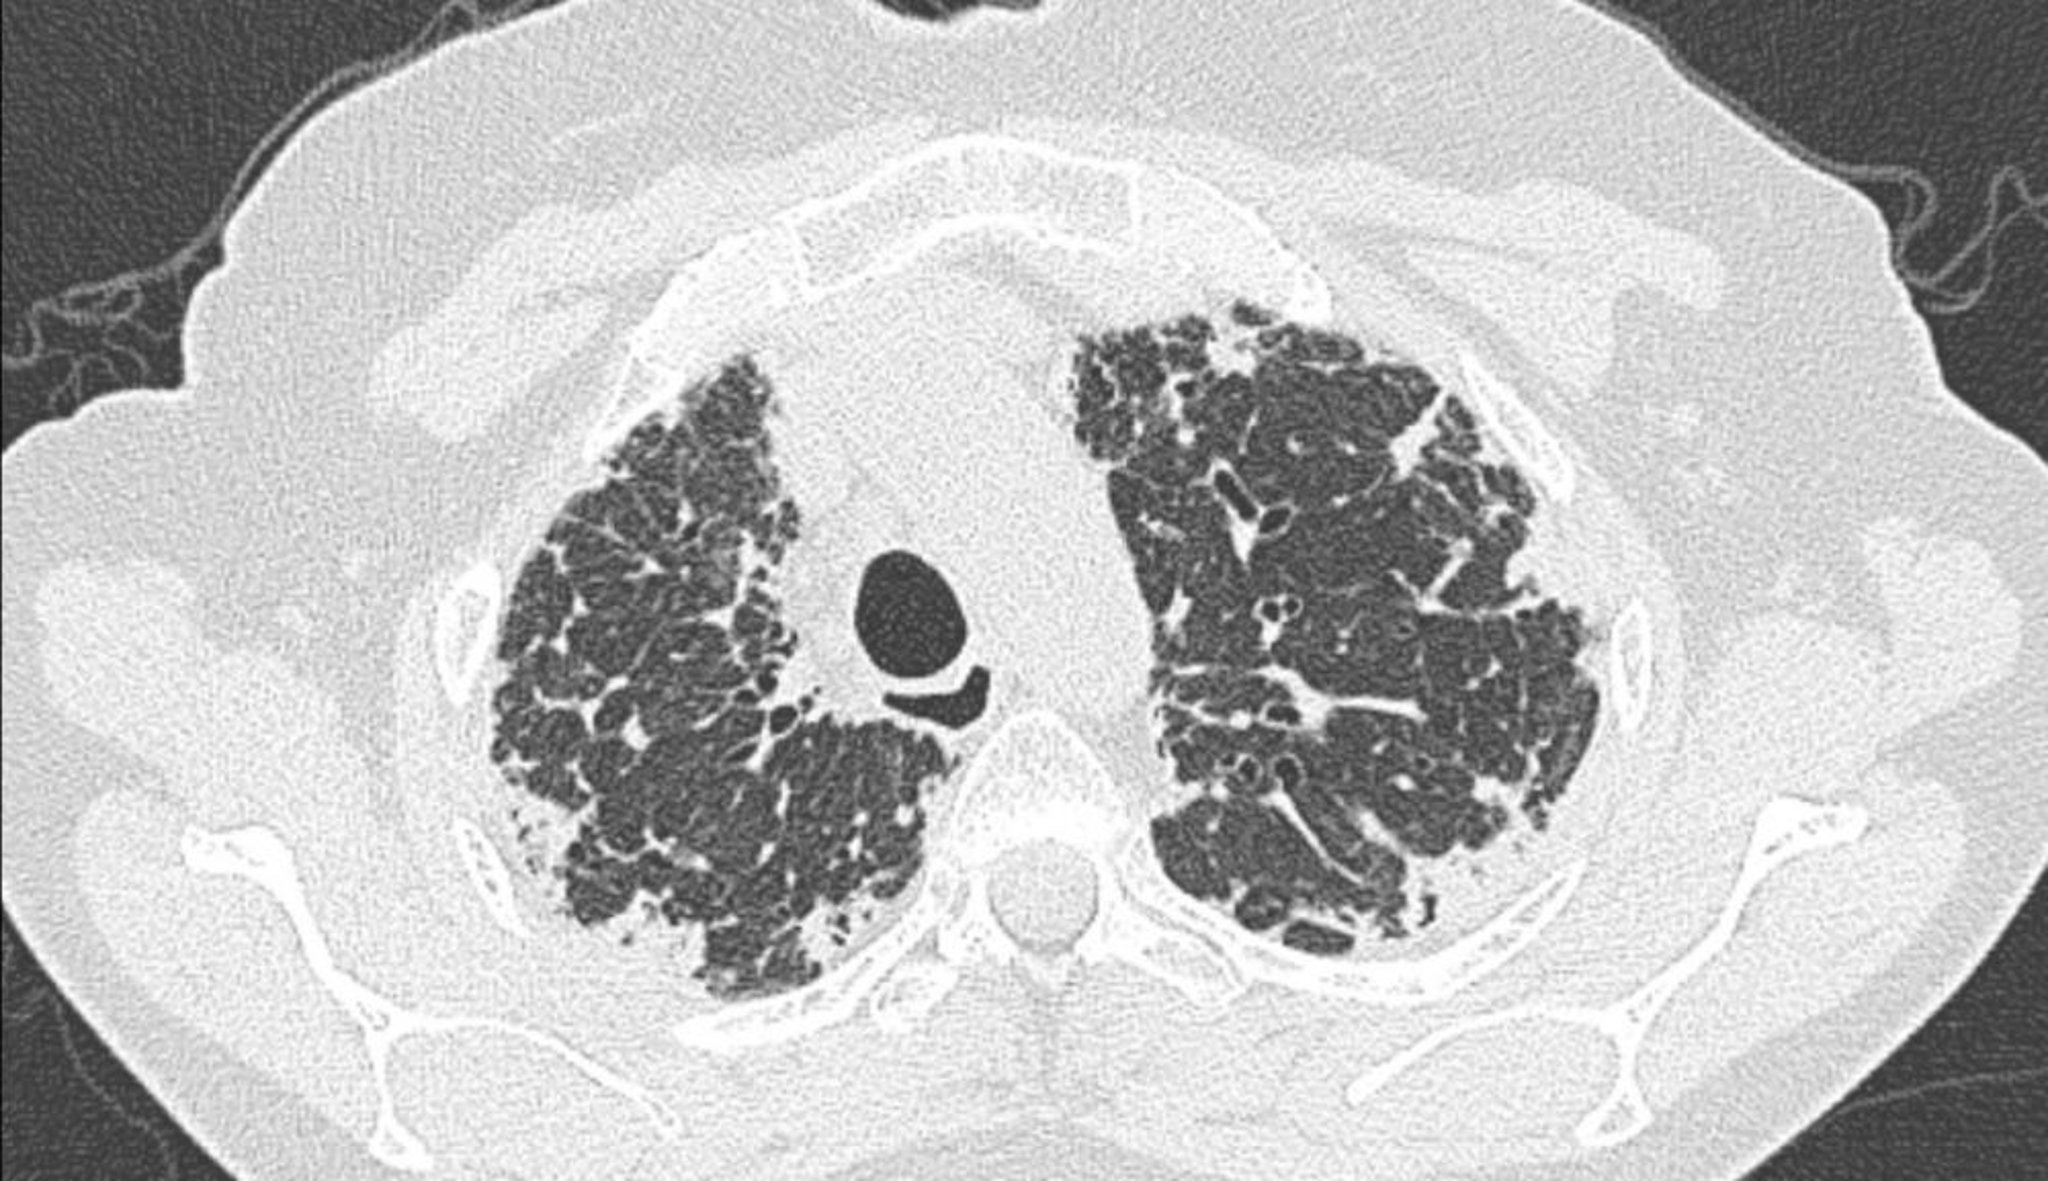

Idiopathic Pleuroparenchymal Fibroelastosis (CT Scan)

CT scan of the chest shows pleural and subpleural thickening.

Image courtesy of Joyce S. Lee, MD, MAS.